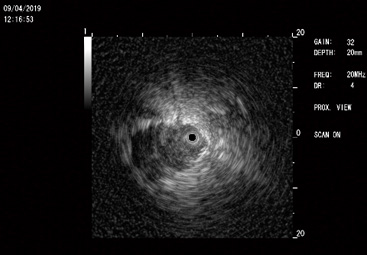

nous avons acquis une nouvelle technique : les minisondes échographiques.

Il s’agit d’une sonde

d’échographie miniaturisée puisque plus petite qu’une allumette en diamètre et

que l’on peut glisser dans le canal opérateur des endoscopes. Comme un radar,

elle tourne sur elle même sur 360° en émettant des ultrasons Poussée

dans les bronches périphériques dans les poumons, elle permet de repérer les

nodules pulmonaires en construisant leur image échographique et permet de les

prélever. C’est une technique complémentaire à la navigation électromagnétique

qui elle construit les images avec les rayons X.

La photo 8 vous montre ainsi un petit nodule détecté. Le

point noir au centre représente la sonde. L’image du nodule est en gris sombre

sur le fond plus blanc du poumon sain qui apparaît selon l’aspect dit « en

tempête de neige »